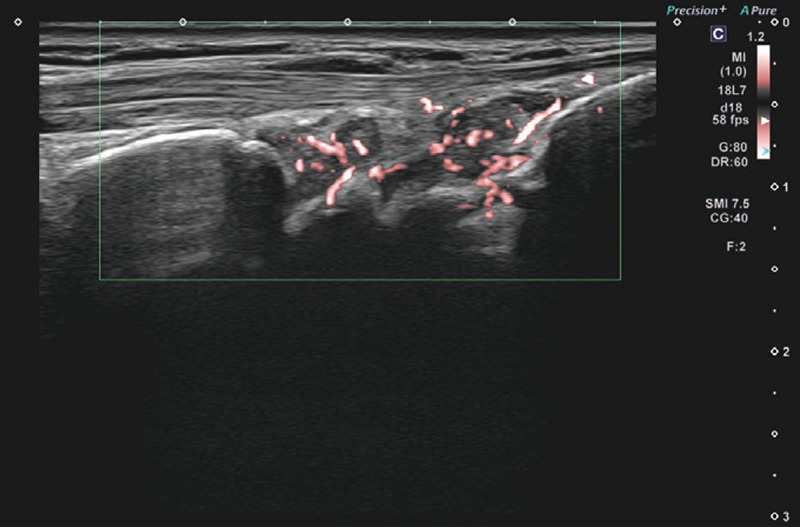

提示した症例画像はAplio meで撮影したRA患者さん手首のBモード画像、SMI画像、パワードプラ画像である。Bモードでは、ご覧の通り滑膜肥厚の低エコー域がクリアに区別できている(画像1)。Superb Micro-vascular Imaging(SMI)の血流は増殖した滑膜の部分に一致しており、血管からのはみ出しもなく血流を正確に検出している(画像2)。パワードプラでは、SMIと比較してブルーミングは存在するものの、モーションアーチファクトがなく、少々あったとしても素早く消失するので、走査時のストレスがなかった(画像3)。もちろんグレード1の血流も正確に検出できる。

RA症例画像

(部位:手首、超音波検査装置:Aplio me)

画像2 SMI 画像2 SMI

画像3 パワードプラ 画像3 パワードプラ